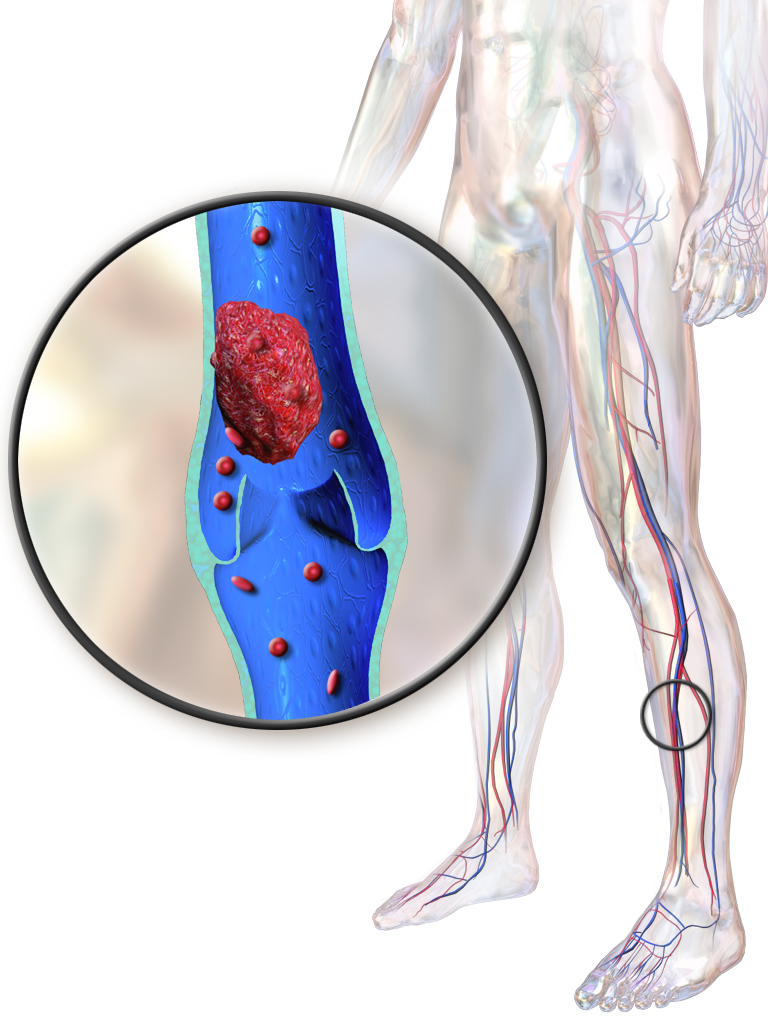

A trombose venosa profunda, ou TVP, é a formação de um coágulo (trombo) dentro das veias profundas da perna. As veias profundas são aquelas que ficam sob os músculos da perna, diferentes das veias superficiais que você vê sob a pele [2].

Normalmente, o sangue flui livremente por essas veias, trazendo oxigênio e nutrientes aos tecidos e retornando ao coração para ser oxigenado nos pulmões. Quando um coágulo se forma, bloqueia parcial ou totalmente esse fluxo, impedindo que o sangue retorne adequadamente. Além disso, existe o risco de que o coágulo se solte e viaje pela corrente sanguínea [2].

Quando o coágulo solto alcança os pulmões, ele pode bloquear a circulação pulmonar, causando uma complicação grave chamada embolia pulmonar (EP). A embolia pulmonar é potencialmente fatal e exige atendimento médico de emergência imediato [2].